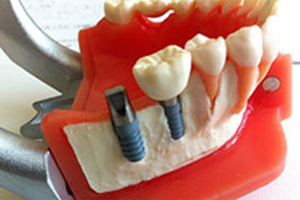

通常インプラント(人工歯根)とは、フィクスチャーとアバットメントが別々に存在し、それらを繋げてから、その上に人工の歯を装着する治療法です。そのため、オペが2回必要となり、構造体も色々と煩雑です。

しかし当院のインプラントは、フィクスチャーとアバットメントが最初から連結された1ピース型インプラントを使用しているため、1回のオペで完結し、頑丈で壊れにくいシンプルな構造となっています。

また、通常のチタンインプラントではなく、HA(ハイドロキシアパタイト)コーティングを施したチタンインプラントのため、骨との結合が早く、治療期間の短縮につながります。しかもインプラント埋入後の初期固定が得られなくとも、骨との固定力が強いため、インプラントの脱落などのリスクが少なく、骨結合の成功率は非常に高いといえます。詳しくはお電話にてお気軽にお問い合わせください。